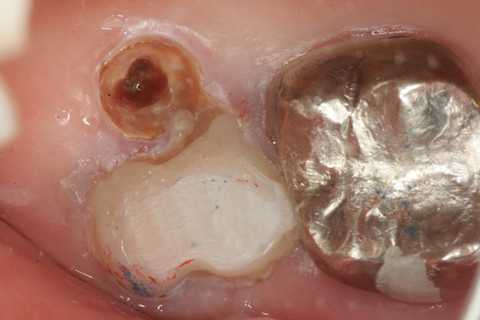

今日の抜歯再植術シリーズ39.2 2025.11.15